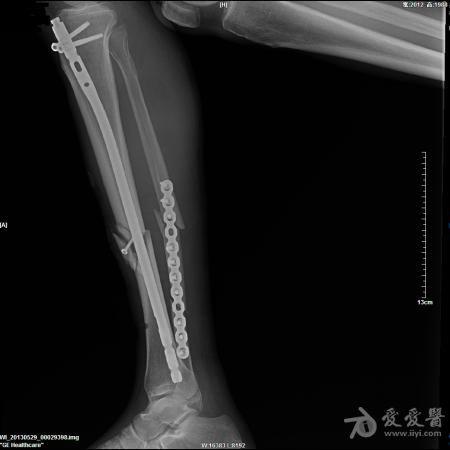

胫骨开放性骨折髓内针固定

57岁男性,骑摩托车摔伤,诊断1.右胫骨开放粉碎性骨折 2.腓骨粉碎性骨折 3.左锁骨粉碎性骨折(近、远端) 4.左肩胛骨粉碎性骨折 5.颅脑外伤。

入院后急诊清创缝合、右跟骨牵引,第9天,颅脑外伤稳定后行手术治疗。

这是术后片,术前片随后奉上。

胫骨髓内固定很好,远端的锁钉看不到了,不明白。至于胫骨的骨块上的螺钉和腓骨的板子,个人愚见纯属多余。

腓骨中断骨折没必要固定,而且固定不是很好。胫骨骨折断端的螺钉画蛇添足,影响愈合

楼主的手术观点可行,只是手术技巧还需进一步提高。1肩部的骨折应是一个浮肩损伤,片上隐约可以看到肩胛颈部的骨折,需要进行悬吊复合体完整性的恢复,或许肩胛骨进行固定效果会更理想。2腓骨骨折涉及到胫腓联合上8CM以内,所以需要固定,但胫腓骨的固定顺序错误,应先固定腓骨。如果术前或术中可以证实胫腓间韧带完整,腓骨的近端骨折可以不固定。3,aap髓钉提供立体的远端锁定,可以选择前后向先置钉。4像这样的带楔形骨块的简单骨折,易造成成骨不良,我更愿意选择双骨双钢板固定。